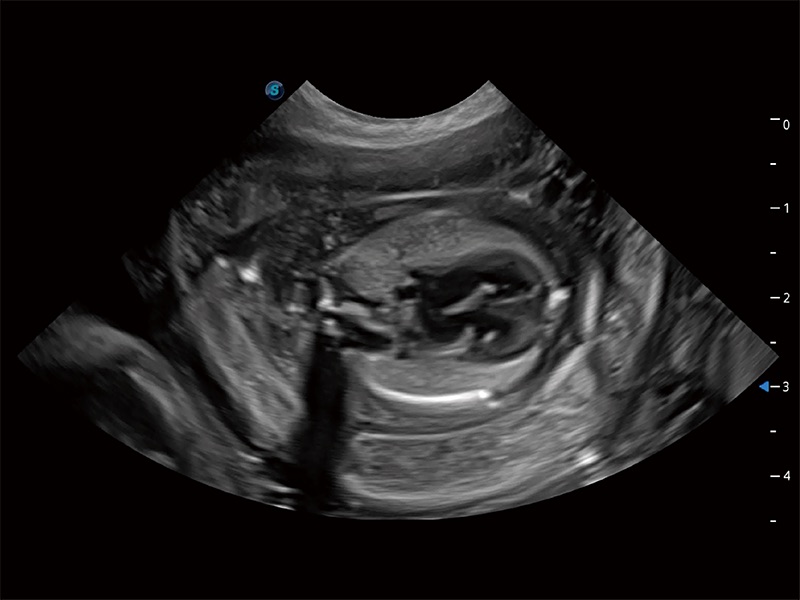

动物是人类最亲密的朋友和最值得信赖的伙伴。milan米兰也一直致力于探索动物专用的超声影像解决方案。全新推出的ProPet系列,是milan米兰在动物超声影像智能化、专业化、精准化的一次跨越式革新。动物不能用言语来表述自己的不适,通过超声影像,ProPet系列搭建了动物医生与不同物种沟通的“桥梁”,为动物医生注入了“治愈之力”。 ProPet 80 是milan米兰匠心打造的一款高端动物专用彩超,采用性能卓越的全新硬件架构,极大提升超声系统的运行效率和数据处理能力,帮助动物医生从容应对日益增多的挑战性病例和日益多样化的临床需求。

高性能和先进的临床应用工具可以为动物医生提供临床信心。ProPet 80 搭载了先进的腹部和浅表应用工具,帮助医生在日常临床实践中发挥前所未有的作用。

ProPet 80 专为动物医生设计,对不同的动物体型和生理结构作出了针对性的优化。通过动物影像专用软件,可满足个性化的应用需求,帮助动物医生获得更精确的诊断数据。